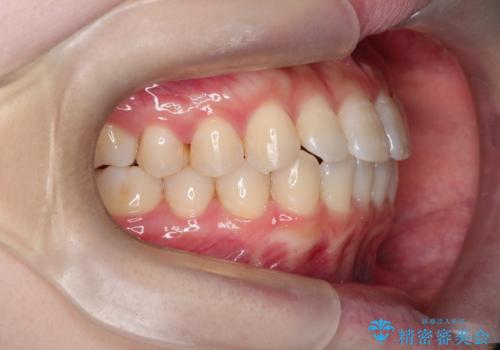

前歯と奥歯のガタガタを矯正で改善

- 患者様は、前歯と奥歯のガタガタ(叢生)を改善し、正面から見た時の歯並びを美しく整えたいとのご要望で来院されました。診断の結果、非抜歯での矯正が可能と判断し、インビザラインを使用する治療計画を立案しました。透明な矯正装置で目立ちにくい治療を行いながら、前歯と奥歯の両方を整列させることを目標にしました。

インビザラインを用いて、前歯の見た目を重視しつつ、奥歯のガタガタも改善しました。特に正面から見た際の美しい歯列を意識し、段階的に歯を移動させることで、全体の調和を図りました。治療中は、適切な装着時間を守ることや、装置の清潔を保つことが重要でした。また、歯肉や歯列全体に無理な負担がかからないように移動を管理しながら治療を進めました。結果として、前歯と奥歯がきれいに並び、見た目にも機能的にも満足いただける仕上がりとなりました。